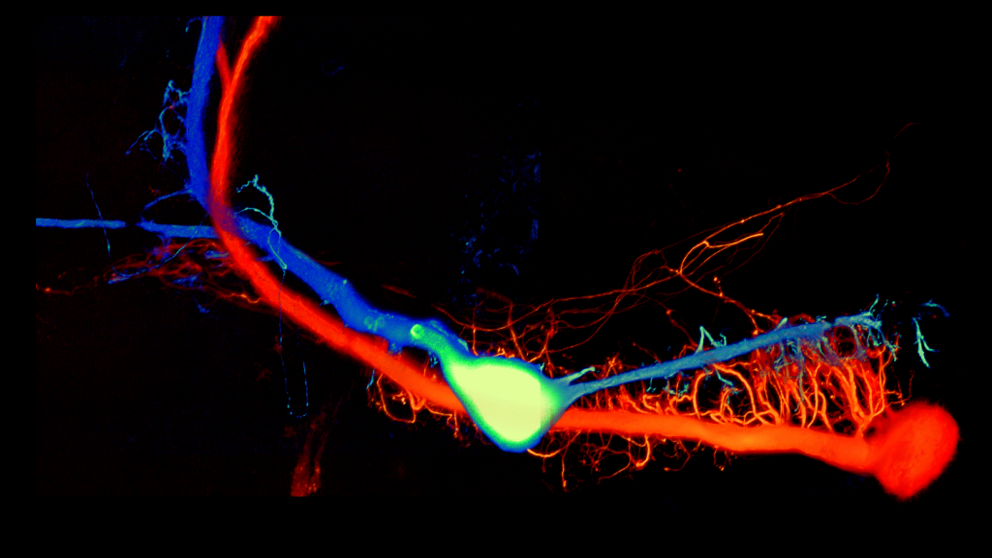

When Neurons talk it's the Calcium that sets the tone

A recent paper published by Dr. Ludwar in Nature Scientific Reports looks at a mechanism brain cells use to switch sensory inputs on and off.